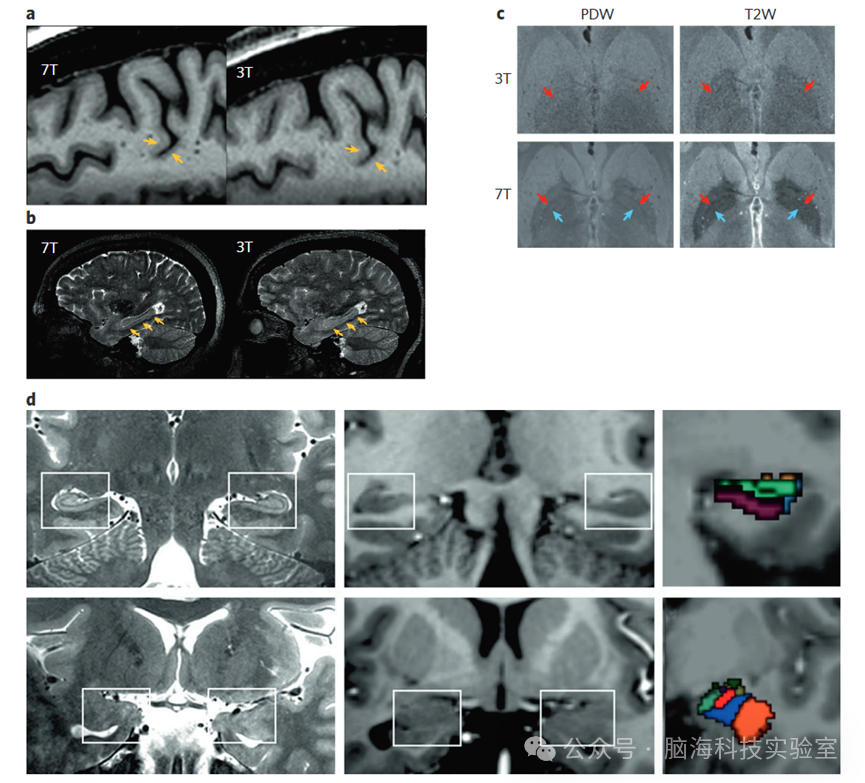

1 3 T7 T的成像采集方法

2 高分辨率结构成像

7T MRI能够通过采集更小的体素且几乎不损失信号质量,实现高分辨率结构数据的获取。常规的7T结构MRI扫描通常在亚毫米级别采样(例如体素尺寸为0.71.0毫米),而专注于成像小解剖细节的研究能够将分辨率提升至500微米,甚至达到375微米的各向同性水平。更高的静态磁场强度能够激发更多的质子,从而产生更强的MRI信号,这些信号更容易从背景噪声中区分出来,从而有效提高了信噪比(SNR)。在神经学诊断的背景下,高空间分辨率的好处已经被很好地描述,但其在精神病学研究中的应用直到最近才开始加速。

7T结构成像的优势来自多个方面。首先,更高的信噪比(SNR)能够实现高空间分辨率,以便精确分割解剖特征并计算结构指标,例如灰质体积和皮层厚度。通过采集更小、更各向同性的体素,这些结构指标的准确性得到提高;7T提供的体素尺寸减小能够通过减少部分容积效应的影响来降低局部体积估计的偏差。其次,与3T相比,7T的磁场强度增加会产生更长的T1弛豫时间,从而增强组织类型之间的对比度,并实现对解剖学上不同的脑区和核团的更准确分割。第三,无论是基于对比度的还是定量结构测量的磁共振序列(如MP2RAGE序列),都更容易应用于7T协议,因为它们受益于超高场强下的高信噪比和对比度。以MP2RAGE为例,它在不同的反转时间(通常包括T1加权和质子密度加权图像)采集两个梯度回波图像,并将它们结合起来生成定量的T1图和基于对比度的均匀(UNI)图像,该图像具有更均匀的强度和更优越的灰白质对比度。这些改进使得解剖定位和分割得到增强(例如,图2ac),对皮层形态的评估更加精确,偏差减少,从而提高了测试-重测的可靠性,并有助于追踪纵向变化,这对于临床研究通常是至关重要的。7T已显示出对临床人群灰质厚度变化的敏感性,例如,识别首发精神病患者中广泛的皮层厚度减少。机器学习方法也显示出在7T下基于灰质和白质测量对患者和对照组进行分类的能力优于3T,从而将实现与3T相当的预测性所需的患者数量减少了30%50%

7T结构成像还提供了更准确地研究小结构的机会,特别是那些具有已知临床相关性的深部和皮层下脑区。一个典型例子是对海马体的增强表征,其中可以在亚毫米结构扫描中准确识别亚区,并采用自动分割方法(图2d)。海马体是重度抑郁症和精神分裂症病理生理学的核心区域,尤其是在精神病早期阶段,体积变化尤为明显。然而,大多数3T研究将海马体视为单一结构,或者仅限于长轴(前后轴)分析。7T的分割验证了精神分裂症中的体积变化,表明CA4/DG是这些减少的主要来源,并与5-羟色胺(5HT1A5-HT4)受体的改变有关。此外,还有研究发现了海马体解剖学上不同的亚区与临床的相关性,例如,将抑郁症患者的体积减少定位于CA2/3,将重度抑郁症对电休克治疗(ECT)的反应定位于齿状回,以及识别与精神病风险相关的心理社会因素(如一生中的压力)的差异性反应。在具有解剖学和功能上不同的亚区的其他皮层下区域中,也取得了类似的解剖学划分的进展。与3T相比,7T对皮层下核团(包括黑质和内外苍白球)的分割提高了可靠性,这使得能够创建高分辨率的解剖图谱。对基底神经节核团的识别,包括苍白球亚段,对于通过改善解剖定位来指导深部脑刺激靶点具有重要意义,这可能会改善临床结果。在杏仁核中,3T研究通常能够识别基底外侧和中央内侧亚区,但7T的高分辨率结构MRI可能支持绘制九个不同的亚核。小结构映射已被应用于临床队列的数据,特别是在重度抑郁症的背景下,显示出临床严重程度与杏仁核亚核体积、缰核和岛叶亚区的关联。

超高场强(UHF)的超高分辨率离体扫描为临床研究提供了机会,包括在低场强下进行的研究。NextBrain组织学图谱提供了全脑的精细解剖细节,包括400微米MRI,用于在标准和UHF MRI研究之间进行比较。其他7T的离体扫描方法甚至进一步推动了这一领域,以100微米的分辨率获取结构数据,从而扩展了识别以前无法通过神经影像学应用获得的解剖特征的机会。然而,7T需要独特的采集方法来控制与超高场成像相关的挑战,例如在包括皮层下区域、颞叶皮层和小脑在内的低部区域的图像强度不均匀性。此外,当进行全脑分析时,高空间分辨率采集可能耗时较长,尽管平面内(GRAPPA)加速和其他参数优化方法可以促进在不到10分钟内完成采集,使其成为临床研究环境中的可行选择。此外,由于7T下的运动伪影可能会因小体素尺寸而放大,因此开发前瞻性运动校正对于超高场临床研究可能特别重要。最后,尽管已经投入了大量工作来开发海马体和杏仁核超高场成像的自动分割方法,例如在高分辨率数据集上训练分类器,但这些方法尚未广泛应用于其他皮层和皮层下结构。此外,为3T结构扫描的去颅骨、分割和解剖划分而开发的神经影像学工具可能并不完全适用于高分辨率7T数据,这突显了继续开发用于高空间分辨率超高场结构数据的公开可用软件的重要性。

图片

不同大脑区域和模式的7 T3 T解剖图像的比较